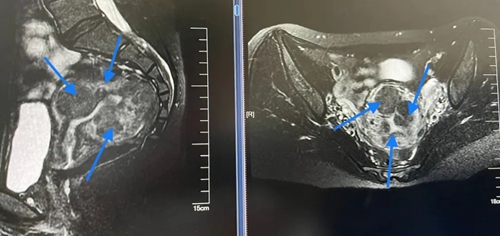

2020年,劉女士到青島婦女兒童醫(yī)院微無創(chuàng)中心就醫(yī)。來院時(shí),劉女士臉色蒼白,面帶愁容。接診醫(yī)生經(jīng)詳細(xì)問診得知,她曾因多發(fā)肌瘤、月經(jīng)量大導(dǎo)致重度貧血,并在當(dāng)?shù)蒯t(yī)院進(jìn)行子宮肌瘤剝除術(shù)。然而,術(shù)后劉女士病情復(fù)發(fā),月經(jīng)量持續(xù)增多。結(jié)合劉女士既往病史及超聲報(bào)告,接診專家婦科中心主任趙淑萍高度懷疑劉女士患有的是較為罕見的彌漫性子宮平滑肌瘤病,而非普通的多發(fā)肌瘤。果然,盆腔核磁共振檢查結(jié)果顯示劉女士子宮上長滿了大大小小的肌瘤,這是彌漫性子宮平滑肌瘤病的典型病癥。

彌漫性子宮平滑肌瘤病是一種特殊類型的子宮肌瘤,多發(fā)生于育齡期女性,特點(diǎn)是大大小小的肌瘤界限不清,累及宮體全層。臨床表現(xiàn)以月經(jīng)量多、痛經(jīng)、壓迫癥狀為主,約80%的患者合并不孕。因肌瘤結(jié)節(jié)可達(dá)數(shù)百、數(shù)千個(gè),很難完全剔除所有肌瘤,因此通常的根治方法是切除子宮。